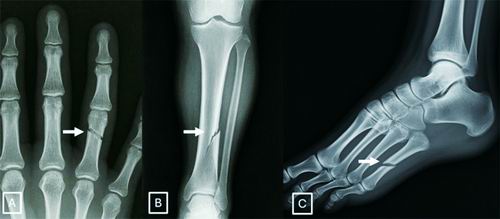

AI生成的X光片让科学家感到担忧。图片来源:北美放射学会

该研究设计了一项互动测试,旨在教会研究人员辨别AI生成的X光扫描图像与真实图像。它涵盖了AI生成的放射影像的一些典型特征,如骨骼过于光滑、脊柱异常笔直等。研究人员指出,除了培训放射科医生,数字水印等技术可以使识别真实图像变得更容易,政府机构主导的监管框架也可以这样做。(王铄)